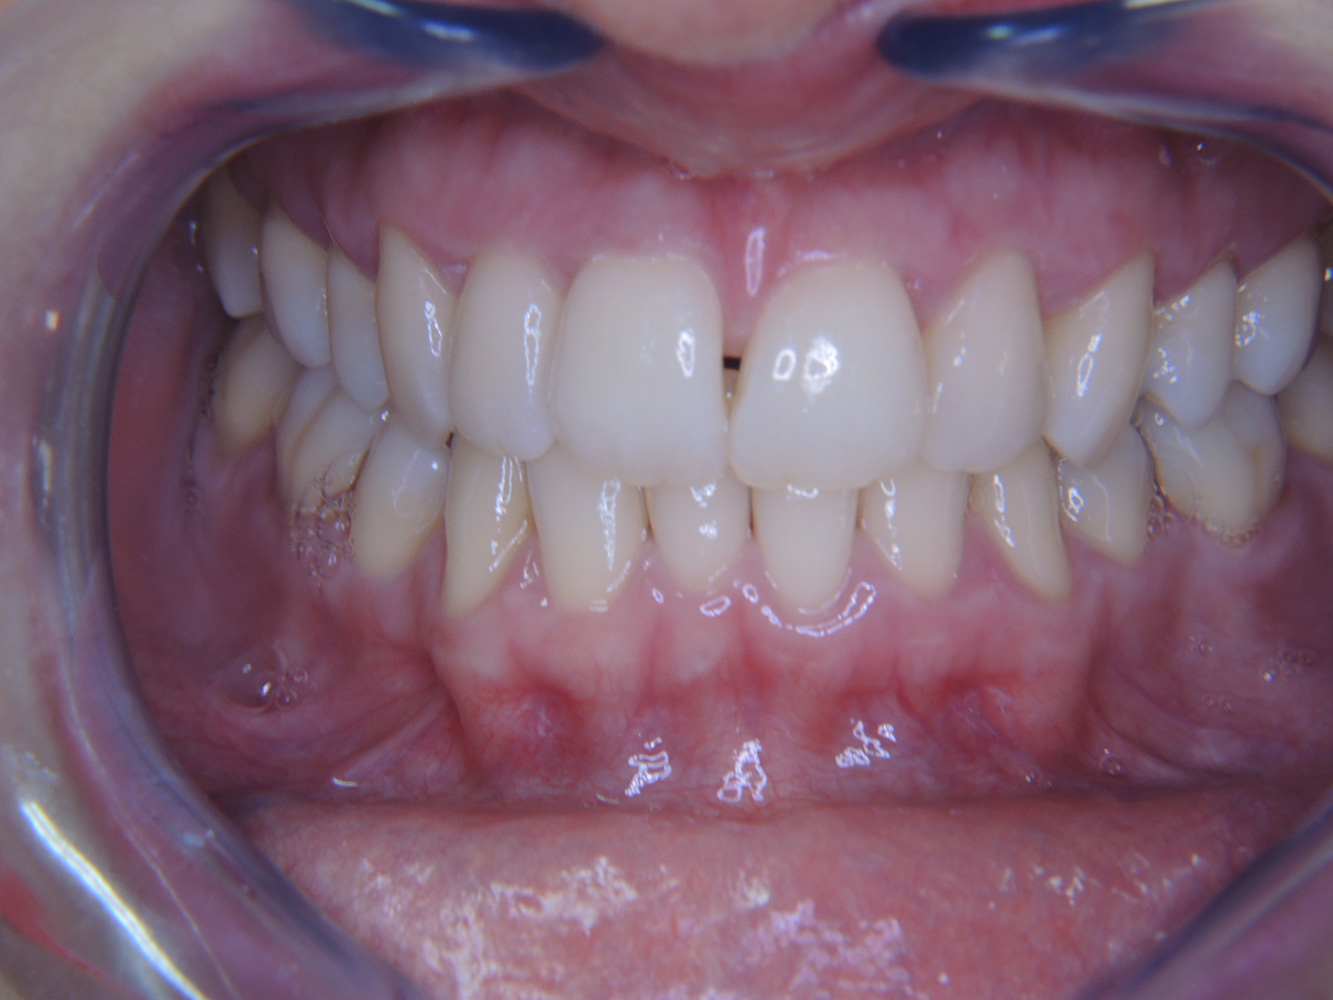

Una paziente diabetica di 51 anni con una buona igiene orale si presenta per una seduta di prevenzione. I valori di glicemia sono stabili con HbA1c = 6,2%, per cui si ritiene che la sua condizione possa essere sufficientemente gestita con la metformina (un farmaco per il trattamento del diabete). La paziente non presenta restauri esistenti o precedenti patologie orali. Sulla base dei referti disponibili si può constatare una gengivite nonostante una condizione altrimenti stabile.

Sebbene i parametri di salute generale e orale siano stabili, la paziente necessita di una seduta di prevenzione personalizzata per via della sua patologia di base. Il diabete mellito è sempre associato a un rischio maggiore di parodontite (12), che tuttavia può essere tenuto sotto controllo con un buon trattamento medico. Il monitoraggio regolare della HbA1c fornisce indicazioni sull'andamento del livello di glicemia nelle ultime otto-dodici settimane, un valore HbA1c ≥ 6,5% indica la presenza di diabete mellito.